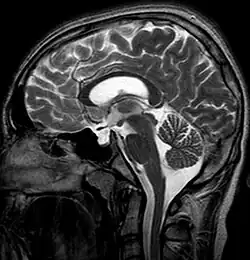

The empty sella sign is a radiological finding characterized by the partial or complete filling of the sella turcica with cerebrospinal fluid (CSF), causing the pituitary gland to appear flattened or compressed against the walls of the sella.[1] This results in the sella appearing "empty" on imaging, despite the presence of a compressed pituitary gland. The empty sella sign is typically identified on magnetic resonance imaging (MRI) or computed tomography (CT) and can be associated with various clinical conditions or incidental findings.[2]

MRI is the gold standard for diagnosing the empty sella sign. Key features include:[5]

- CSF signal: The sella turcica is filled with material that follows the signal characteristics of CSF on T1-weighted and T2-weighted images.

- Flattened pituitary gland: The pituitary gland appears thin and plastered against the sellar floor or walls.

- Enlarged sella: The sella turcica may appear expanded or normal in size.

On CT, the empty sella sign may appear as hypodensity in the sella, corresponding to CSF. There may be possible sellar floor thinning or remodeling due to chronic pressure changes.